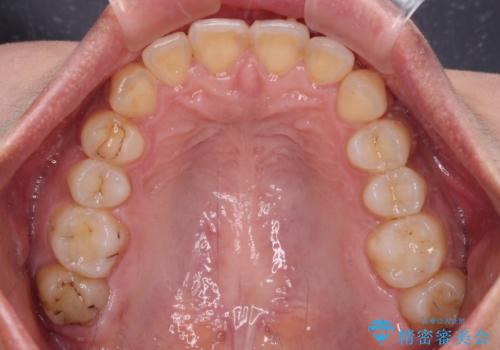

深い咬み合わせと前歯のデコボコ インビザラインによる矯正治療

治療途中では、左右ともに奥歯が咬みにくい状態が続き、問題なく噛めるようになるまでに長期間を要しました。

一方で、デコボコや下顎の前歯が隠れてしまうほどの深い咬み合わせはしっかりと改善されました。